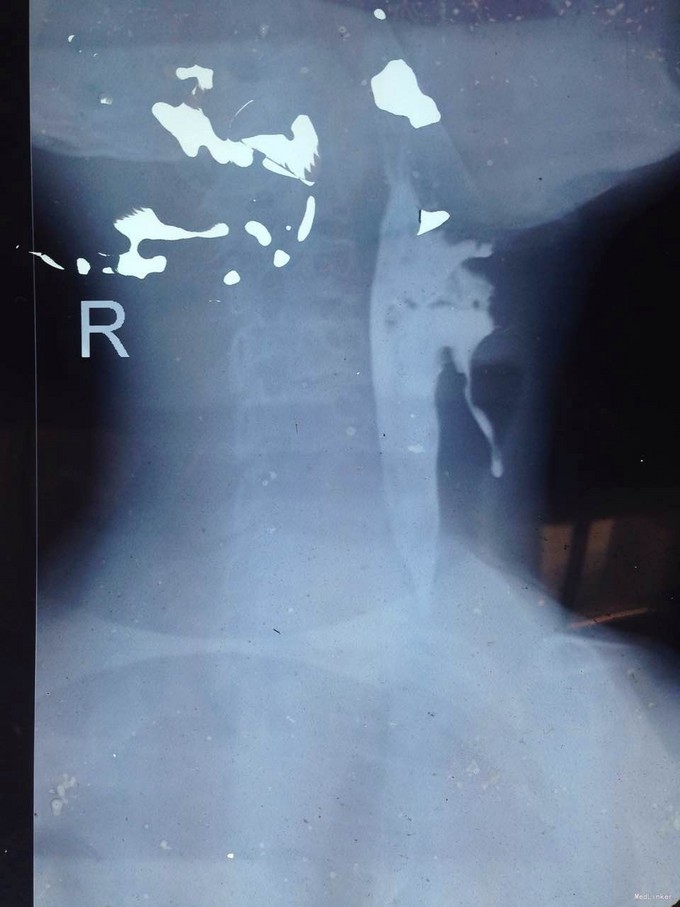

该患者在诊断上是有些困难,颈部多发脓肿是明确的,但是瘘口的位置不好确定,从而未能确诊,8年前患者行上消化道钡餐检查,诊断“食管瘘”,但是我们从8年前的影像上看,瘘口的位置太高,不像是食管的瘘口,考虑是不是梨状窝的瘘道,为了进一步确诊,我们给患者行了胃镜检查,结果胃镜发现左侧梨状窝有1个3mm大小的小孔,胃镜未能通过,食管未见明显的瘘口。为了更加明确瘘口的位置,我们与影像科商议后决定口服造影剂后行颈部CT平扫,因怕钡餐沉积在脓肿内不好排出,我们采用了口服碘化油。此次影像明确了瘘口的确在左侧梨状窝。最终诊断:左侧颈部多发脓肿;左侧梨状窝瘘道形成。 治疗:入院后予抗感染、禁食、营养支持等治疗,患者感染得以控制,请耳鼻咽喉科会诊后建议转科治疗。